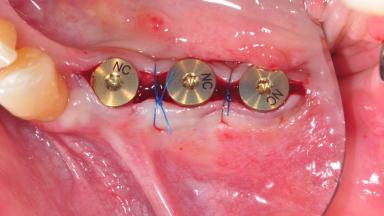

After the placement of three diameter-reduced two-piece implants the bone is augmented with autologous bone chips and DBBM particles to enlarge the crest volume. The surgery is completed with the application of two membrane layers and primary wound closure.

For soft tissue management, the initial healing caps are replaced with a longer type 8 weeks after implant placement in a second intervention before prosthodontic treatment is initiated.